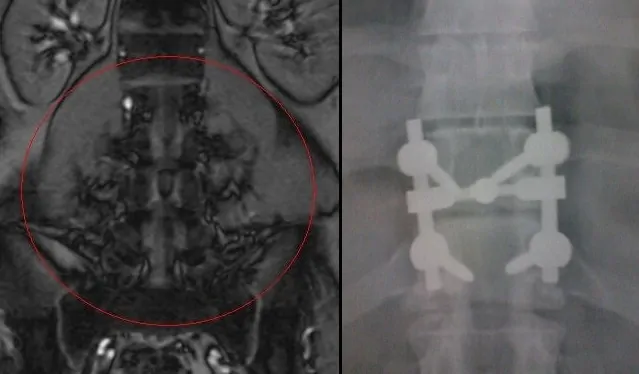

Por volta de 2009, Deus colocou um médico neurologista em minha vida, que assumiu meu caso, achou um indicação clínica para os sintomas, uma compressão de medula em D11 e D12, onde depois de muitos e muitos exames de eletroneuromiografia, RM, ele constatou que o caso era cirúrgico. Me indicou então, para uma das melhores equipes de neurocirurgiões em coluna do Rio de Janeiro e após cumprir todas as carências e claro, entrar na justiça contra o plano de saúde, operei em julho de 2010. Ai já tinha engordado de novo, mas, já havia parado de beber, e após a cirurgia, com o processo de reabilitação, fisioterapia, comerei a pedalar. Decidi que iria cuidar e buscar uma qualidade de vida melhor para a minha condição, passei a andar com uma muleta de apoio (a Cremilda) e digo que ela é realmente a única mulher que me apoia (rsrsrs), e em julho de 2011 conheci o Sait´s (Studio de Atendimento Integrado de tratamento a Saúde) e desde então estou lá, com trabalhos específicos para as minhas partes piores. Decidi em me dedicar de verdade e hoje, treino, faço dieta, descanso, me suplemento e busco levar uma vida o mais saudável possível, dentro das minhas condições e das minhas limitações.